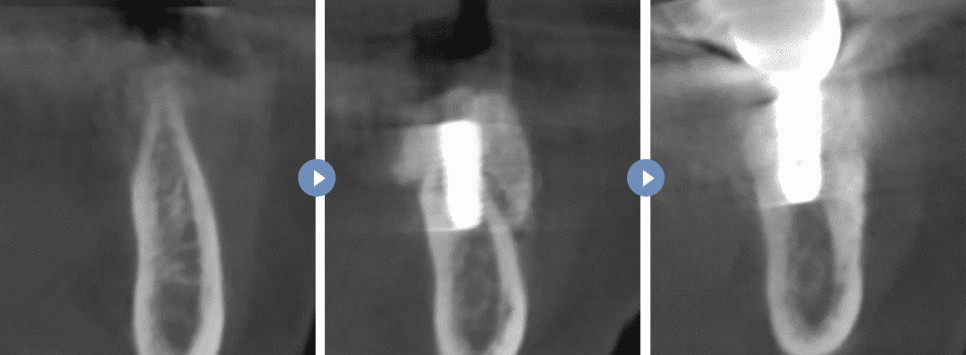

뼈이식 수술(노출형)

수술 전 CT단면 > 노출형 뼈이식 후 CT 단면 > 뼈이식 최종 완성 후 CT 단면